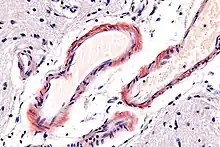

| Micrograph of cerebral amyloid angiopathy using congo red stain | |

Cerebral amyloid angiopathy (CAA) is a form of angiopathy in which amyloid beta peptide deposits in the walls of small to medium blood vessels of the central nervous system and meninges.[2][3] The term congophilic is sometimes used because the presence of the abnormal aggregations of amyloid can be demonstrated by microscopic examination of brain tissue after staining with Congo red. The amyloid material is only found in the brain and as such the disease is not related to other forms of amyloidosis.[4]